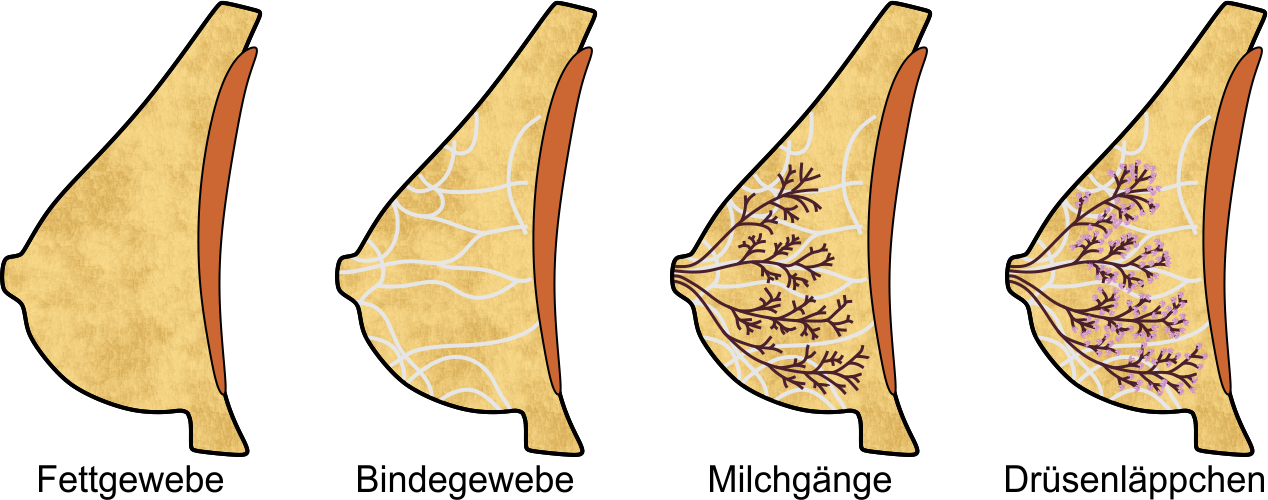

Die weibliche Brust

Die weibliche Brust besteht in Hauptsache aus den vier Komponenten Fettgewebe, Bindegewebe, und den Milchgängen und Milchdrüsenläppchen, die zusammen die Brustdrüse bilden:

Das Fettgewebe gibt der Brust ihre Form, das Bindegewebe durchzieht die Brust in gewölbten, fächerartigen Bahnen und verleiht ihr Stabilität. Die Milchgänge leiten die Milch zur Brustwarze, und in den Drüsenläppchen wird die Milch gebildet; die rotbraune Fläche in den obigen Abbildungen symbolisiert den Brustmuskel.

Aufbau der Brustdrüse

Die Brustdrüse gliedert sich in 10 bis 16 Drüsenlappen, im obigen Bild sind vier davon dargestellt. Ein Drüsenlappen lässt sich gut mit einem Baum vergleichen:

Der Stamm des Baums endet in der Brustwarze, seine Äste und Zweige entsprechen den Milchgängen, und die Blätter bilden die Milchdrüsenläppchen. Die 'Blätter' sind allerdings nicht flach, sondern sehen eher wie Himbeeren mit einem kurzen Stiel aus - hier eine Sicht durch das Mikroskop:

Der Stamm des Baums endet in der Brustwarze, seine Äste und Zweige entsprechen den Milchgängen, und die Blätter bilden die Milchdrüsenläppchen. Die 'Blätter' sind allerdings nicht flach, sondern sehen eher wie Himbeeren mit einem kurzen Stiel aus - hier eine Sicht durch das Mikroskop:

Die vier oben genannten Gewebearten sind in ihren Anteilen in jeder Brust individuell angelegt. Die meisten Frauen haben eine ausgewogene Verteilung, bei manchen kann jedoch eine bestimmte Gewebeart überwiegen. Dazu verändert sich die Brust mit zunehmendem Alter, die Milchgänge und das Bindegewebe werden vor allem nach dem Wechsel dünner, die 'Blätter' des Baums 'verwelken' - die Drüsenläppchen schrumpfen also, und der Fettgewebeanteil wird größer. Üblicherweise entwickeln sich diese Veränderungen von innen nach außen, und von unten nach oben.

Tumore können aus allen vier Gewebearten hervorgehen. Tumore des Binde- und Fettgewebes sind zumeist gutartig, Tumore der Milchgänge und Drüsenläppchen sind meist bösartig. Diese Tumore werden üblicherweise als Brustkrebs bezeichnet.